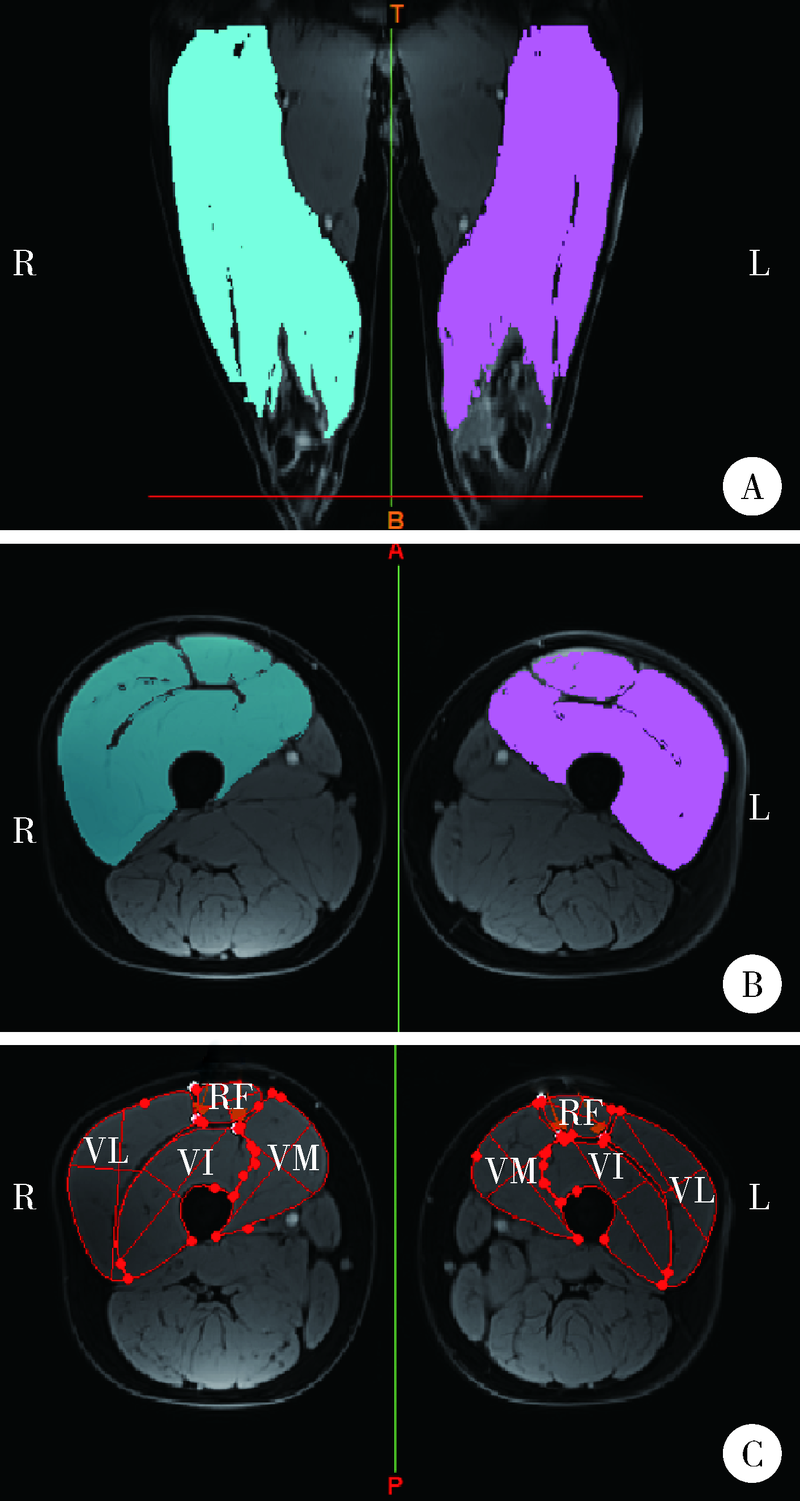

| 图1 图像分析软件中的受试者MRI图像 |

| Figure 1 The MRI images of the participants in the image analysis software A, the establishment of the quadriceps mask (the threshold is 60); B, the area encircled in color shows the quadriceps CSA in both sides; C, the regions with red line show the rectus femoris (RF), vastus medialis (VM), vastus internus (VI), vastus lateralis (VL), respectively. |